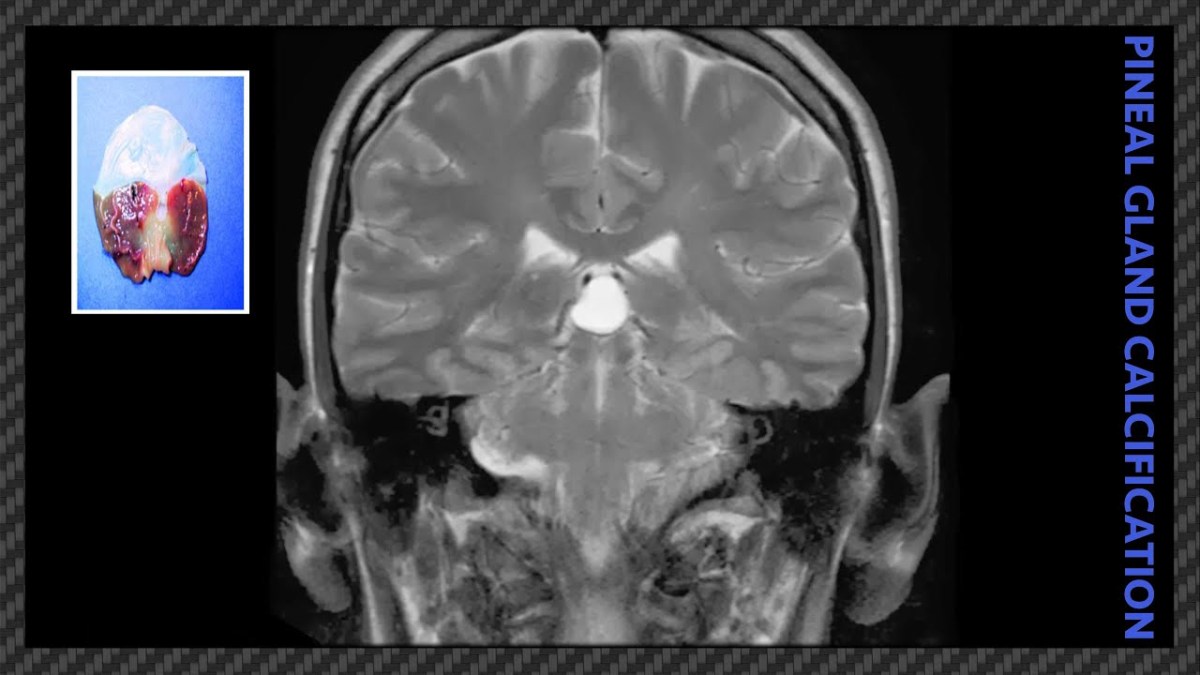

What Is Pineal Gland Calcification

Calcification of the Pineal Gland is an unknown process by which minerals, primarily calcium & fluoride, are deposited in the Pineal Gland, resulting in the Calcification of the Pineal Gland. One estimate stated that 40% of the US population experiences Calcification by age 17 and has been identified in children as young as 2 years old.